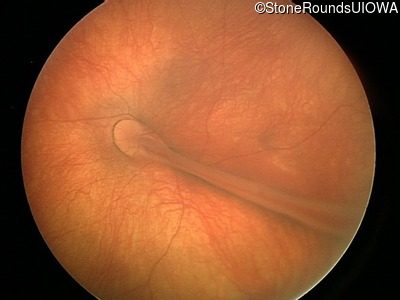

Fundus Photography - Right - 20/125

Exemplar